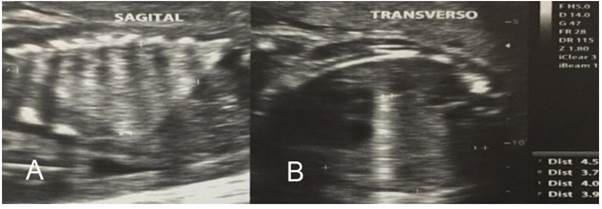

Se evaluó un caso en el Hospital de Especialidades de Izamba (Ambato), donde se observó en un embarazo de 24 semanas mediante ultrasonografía, que presentó una lesión en el pulmón derecho hiperecogénica con una longitud de 5 cm, cuya evaluación de la relación de volumen de malformación congénita de las vías respiratorias pulmonares (Congenital Pulmonary Airway Malformation Volume Ratio - CVR), resultó en 3.1, que representa un alto riesgo para hidropesía fetal (hidrops fetal). Se observó también desviación del mediastino del feto como resultado del desplazamiento provocado por la tumoración.

En la figura 1 A se muestra un corte sagital de tórax de embrión de 24 semanas, donde se observa imagen hiperecogénica que abarca la totalidad del pulmón derecho del feto. En la figura 1 B, el corte es transversal, en el que se observa la afectación de todo el pulmón derecho. Se comprobaron estos resultados mediante estudio de resonancia magnética nuclear. De acuerdo al tamaño de la masa tumoral y la valoración de la alta probabilidad de producir hidrops fetal, se decidió la administración de 12 mg de betametasona intramuscular a la madre a las 24 y 26 semanas.

Figura 1. A. Corte sagital de embrión de 24 semanas. B. Corte transversal de embriön de 24 semanas.